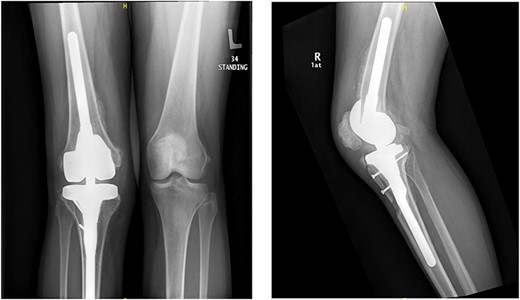

A 32-year-old female known case of rheumatoid arthritis affecting both knees presented to our clinic complaining of severe right knee stiffness post TKA 4-years-ago done in an outside facility (Figs. 1 and 2). She lives in a rural community and was on hydroxychloroquine, but her disease was active as she was not compliant to her medication. On physical examinations, the right knee was larger in size compared to the left knee without joint effusion. Range of motion was zero on flexion, −10° in extension. Standing knee X-ray showed HO around the prosthesis (Fig. 2). Computed tomography (CT) demonstrated extensive HO with implants fixed in place (Fig. 3). Revision surgery and replacement of the prostheses was considered to restore function.

Preoperative standing X-ray showing heterotopic ossification around the prosthesis with preserved knee joint. (A) Heterotopic bone extending proximally on the anterior surface of the femur. (B) Posterior heterotopic bone fusing the knee joint. Careful removal with osteotomes and bone curettes was necessary to remove the old implants.